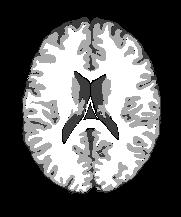

Magnetic Resonance Imaging (MRI) is a critical and widely used medical modality due to its noninvasive nature and ability to produce high-quality images of human organs and tissues. Segmentation in MRI refers to the process of dividing the acquired image data into specific tissues or regions of interest (ROIs). In the context of brain slice MRI data, this often involves distinguishing between cerebrospinal fluid (CSF), gray matter (GM), and white matter (WM), in 2D image slices as depicted in Fig. 1. Research topics on brain anatomy and functionality (e.g., Alzheimer’s disease, tumor detection, neurodegenerative processes, etc.) demand reliable segmentation tools since their outcomes directly impact the subsequent analysis of the brain slice MRI. Therefore, the development of any accurate MRI segmentation framework has to deal with the following issues:

| brain MRI slice | artifacts | ground truth | cartoon | texture |

(1) where can be interpreted as a smoother version of . With a little abuse of notation, we indicate the equation (1) as a cartoon-texture (CT) decomposition (even though we do not aim to compute a proper CT decomposition), where is the ‘cartoon’ depicting the structural component, and the ‘texture’ part including oscillatory components, like texture and noise, as shown in Figure 1.